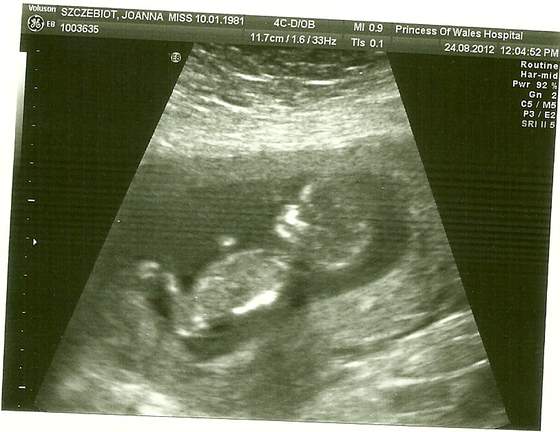

Zobacz załącznik 506927 18+2 wg OM